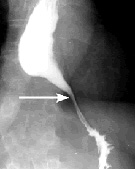

贲门失弛缓症上消化道造影显示食管下端呈鸟嘴状